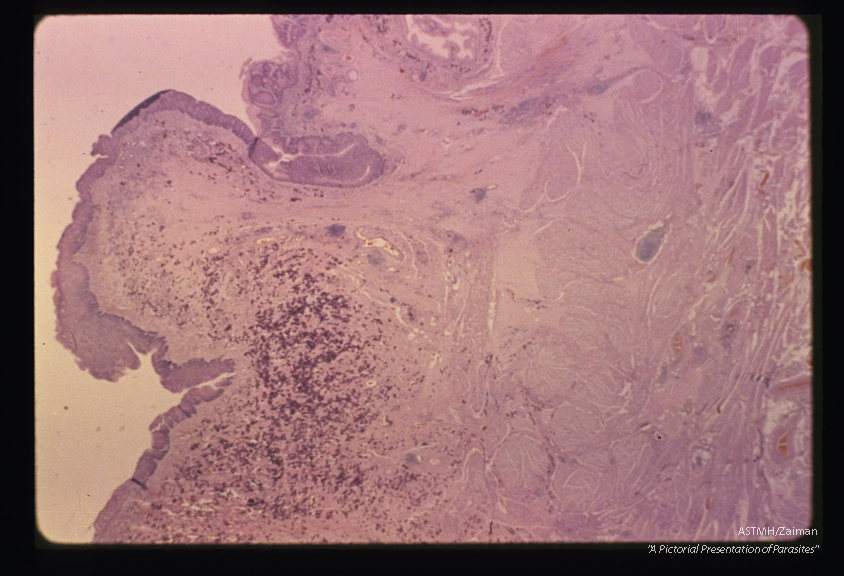

Polyp formation and squamous cell metaplasia in a human urinary bladder heavily infiltrated with ova.

Schistosoma haematobium

Description: Polyp formation and squamous cell metaplasia in a human urinary bladder heavily infiltrated with ova.